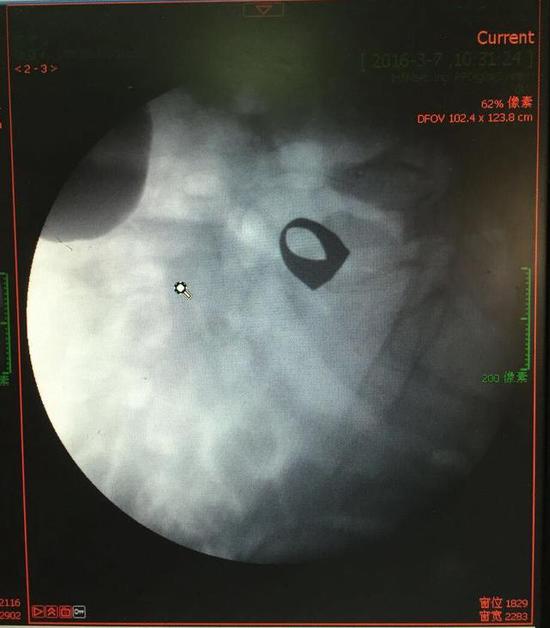

考慮到患者年齡較大,有冠心病,曾經(jīng)中過風(fēng),高血壓極高危級,遂把老人安排在帶有監(jiān)護(hù)的病房,立即給予吸氧,補(bǔ)液等治療。醫(yī)院立刻開啟綠色通道,醫(yī)護(hù)人員專門陪伴病人做了增強(qiáng)CT,腹部平片,和碘水造影,確定戒指的位置。檢查結(jié)果提示戒指位于右下腹小腸內(nèi),距回盲瓣體表投影約5cm。

3月9日,夏澤鋒教授細(xì)心的給病人做結(jié)腸鏡檢查,找到回盲瓣,調(diào)整結(jié)腸鏡鏡頭,快速的進(jìn)入小腸。結(jié)腸鏡緩緩上行至距離回盲瓣5cm的小腸,沒有戒指。繼續(xù)上行,至20cm的地方,仍然沒有找到戒指。

此時(shí)一個(gè)又一個(gè)大大的疑問出現(xiàn)在每個(gè)在場的醫(yī)護(hù)人員腦海中,戒指還在小腸里嗎?戒指在哪個(gè)位置呢?夏教授立刻聯(lián)系放射科,拍片子,發(fā)現(xiàn)戒指已經(jīng)移動了,從右側(cè)移動到了左側(cè)去了。放射科醫(yī)師建議,戒指有可能會繼續(xù)沿腸道下行,如果過了回盲瓣,就可以自行排出,免除手術(shù)痛苦。教授們采納了這個(gè)意見,立即給予促進(jìn)胃腸道動力藥,枸櫞酸莫沙必利片,每日口服三次,另外配合灌腸治療,促進(jìn)腸道蠕動,利于戒指排出。